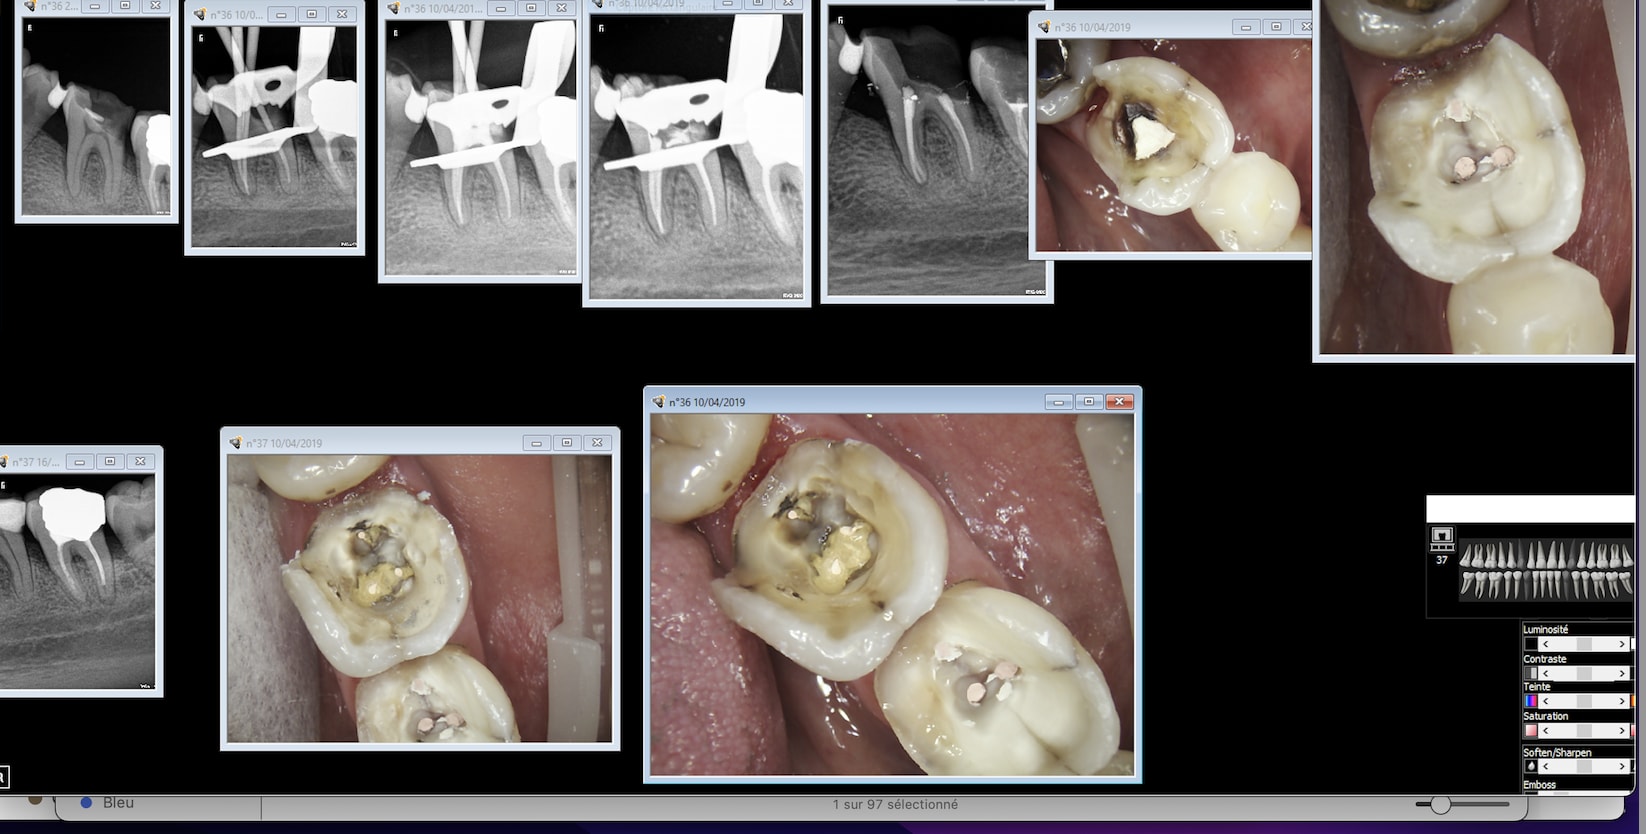

Tiens juste pour le fun 2 onlays CMU les premiers et les derniers faut arreter de nous prendre pour des cons. -)

H96p1fkq1twrapj0y54q3ys9689e - Eugenol

Qcqdcnsy84zqc109zc42sywlvs9t - Eugenol